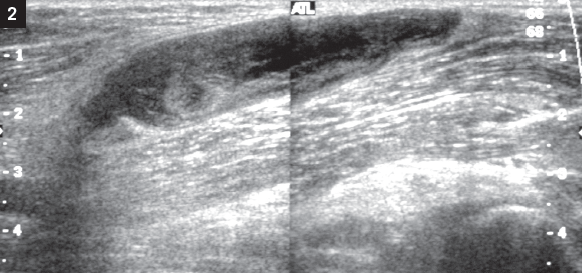

For several days, a 38-year-old man has had an increasingly painful swelling behind the right knee. He runs several times a week. He has hypertension but no history of trauma or periods of inactivity, and no chest discomfort or shortness of breath. He drinks alcohol occasionally but does not use tobacco or illegal drugs.

Examination reveals a swollen soft tissue mass in the posterior popliteal fossa and an intact popliteal pulse. Sensation is intact; range of motion is minimally reduced with knee flexion. There is no erythema or warmth.

Vascular ultrasonography (Figure 2) revealed a Baker (popliteal) cyst, the most common mass of the popliteal fossa. First described in 1877 by Dr William Baker, this synovial cyst results from fluid distention of the gastrocnemius-semitendinosus bursa. Baker cysts lie between the tendons of the medial head of the semimembranous and gastrocnemius muscles, posterior to the femoral condyle. These cysts affect both sexes and all races. Although they are sometimes seen in children, especially those with juvenile rheumatoid arthritis or trauma, they typically affect adults.

The diagnosis may be confirmed by ultrasonography, CT, arthroscopy, or MRI. Treatment involves assisted weight bearing, anti-inflammatory agents, and ice. Arthroscopy is useful for internal derangements of the knee.

About 0.2% to 11% of patients with Baker cyst have coexisting DVT. Therefore, DVT must be ruled out in patients who are undergoing ultrasonography to identify a possible Baker cyst.